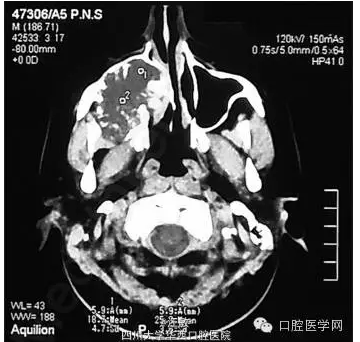

檢查發(fā)現(xiàn)患者面部不對稱,右顴骨區(qū)腫脹??趦葯z查發(fā)現(xiàn)右上頜第一磨牙至第三磨牙處牙齦腫脹,表面光滑,色暗紅。CT顯示病損已波及鼻腔外側壁和鼻中隔。

CT